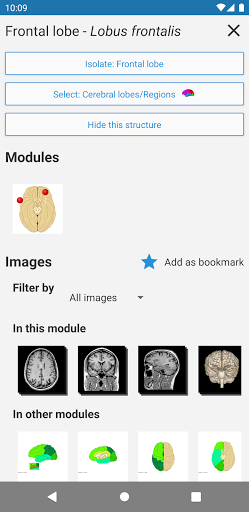

*Improved detail view of anatomical parts for easier identification in images of the current and other modules.

-In the details view of an anatomical structure related terms are now displayed

-Within the details view of an anatomical structure, a pin now points the related structure in all present images

-New option to expand image galleries in the anatomical structure information screen.

- “Filter by”, in the details view you can now filter the images containing the anatomical structure by modality

- “Filter by”, in the details view you can now filter the images containing the anatomical structure by modality

- You can now hide structures one by one (new button inside the description popup) and display them again in the right menu